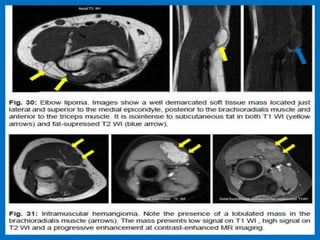

The radiocapitellar line does not pass through the capitulum.

In this case the ulna is also dislocated from the trochlea.

Lateral epicondylitis.

Partial tear. Complete tear.

Tennis elbow.

Medial epicondylitis (Golfer's elbow). Coronal fat-suppressed proton

density-weighted MR images . On the left image, a partial tear of

the common flexor tendon (white arrow) is observed. On the right

image, the common flexor tendon origin is usually thickened and

shows increased signal intensity (yellow arrow).Note the presence of

subtle bone marrow edema in the medial epicondyle (blue arrow).